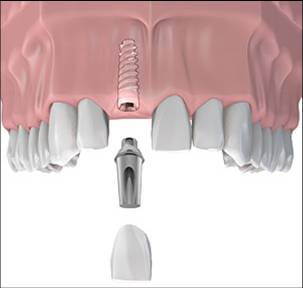

Dental Implants

"How pleasantly surprised I was to be pain free after the implant procedure. I thought I would be in a lot more pain than I actually was..." Read more-

"Implants are made of biologically compatible materials which have undergone extensive testing over a period of several years. Since these materials are largely metals, such as titanium, and have never been living tissue, there is no likelihood of causing an antigen-antibody response which could cause rejection similar to that which sometimes occurs with heart and kidney transplants".